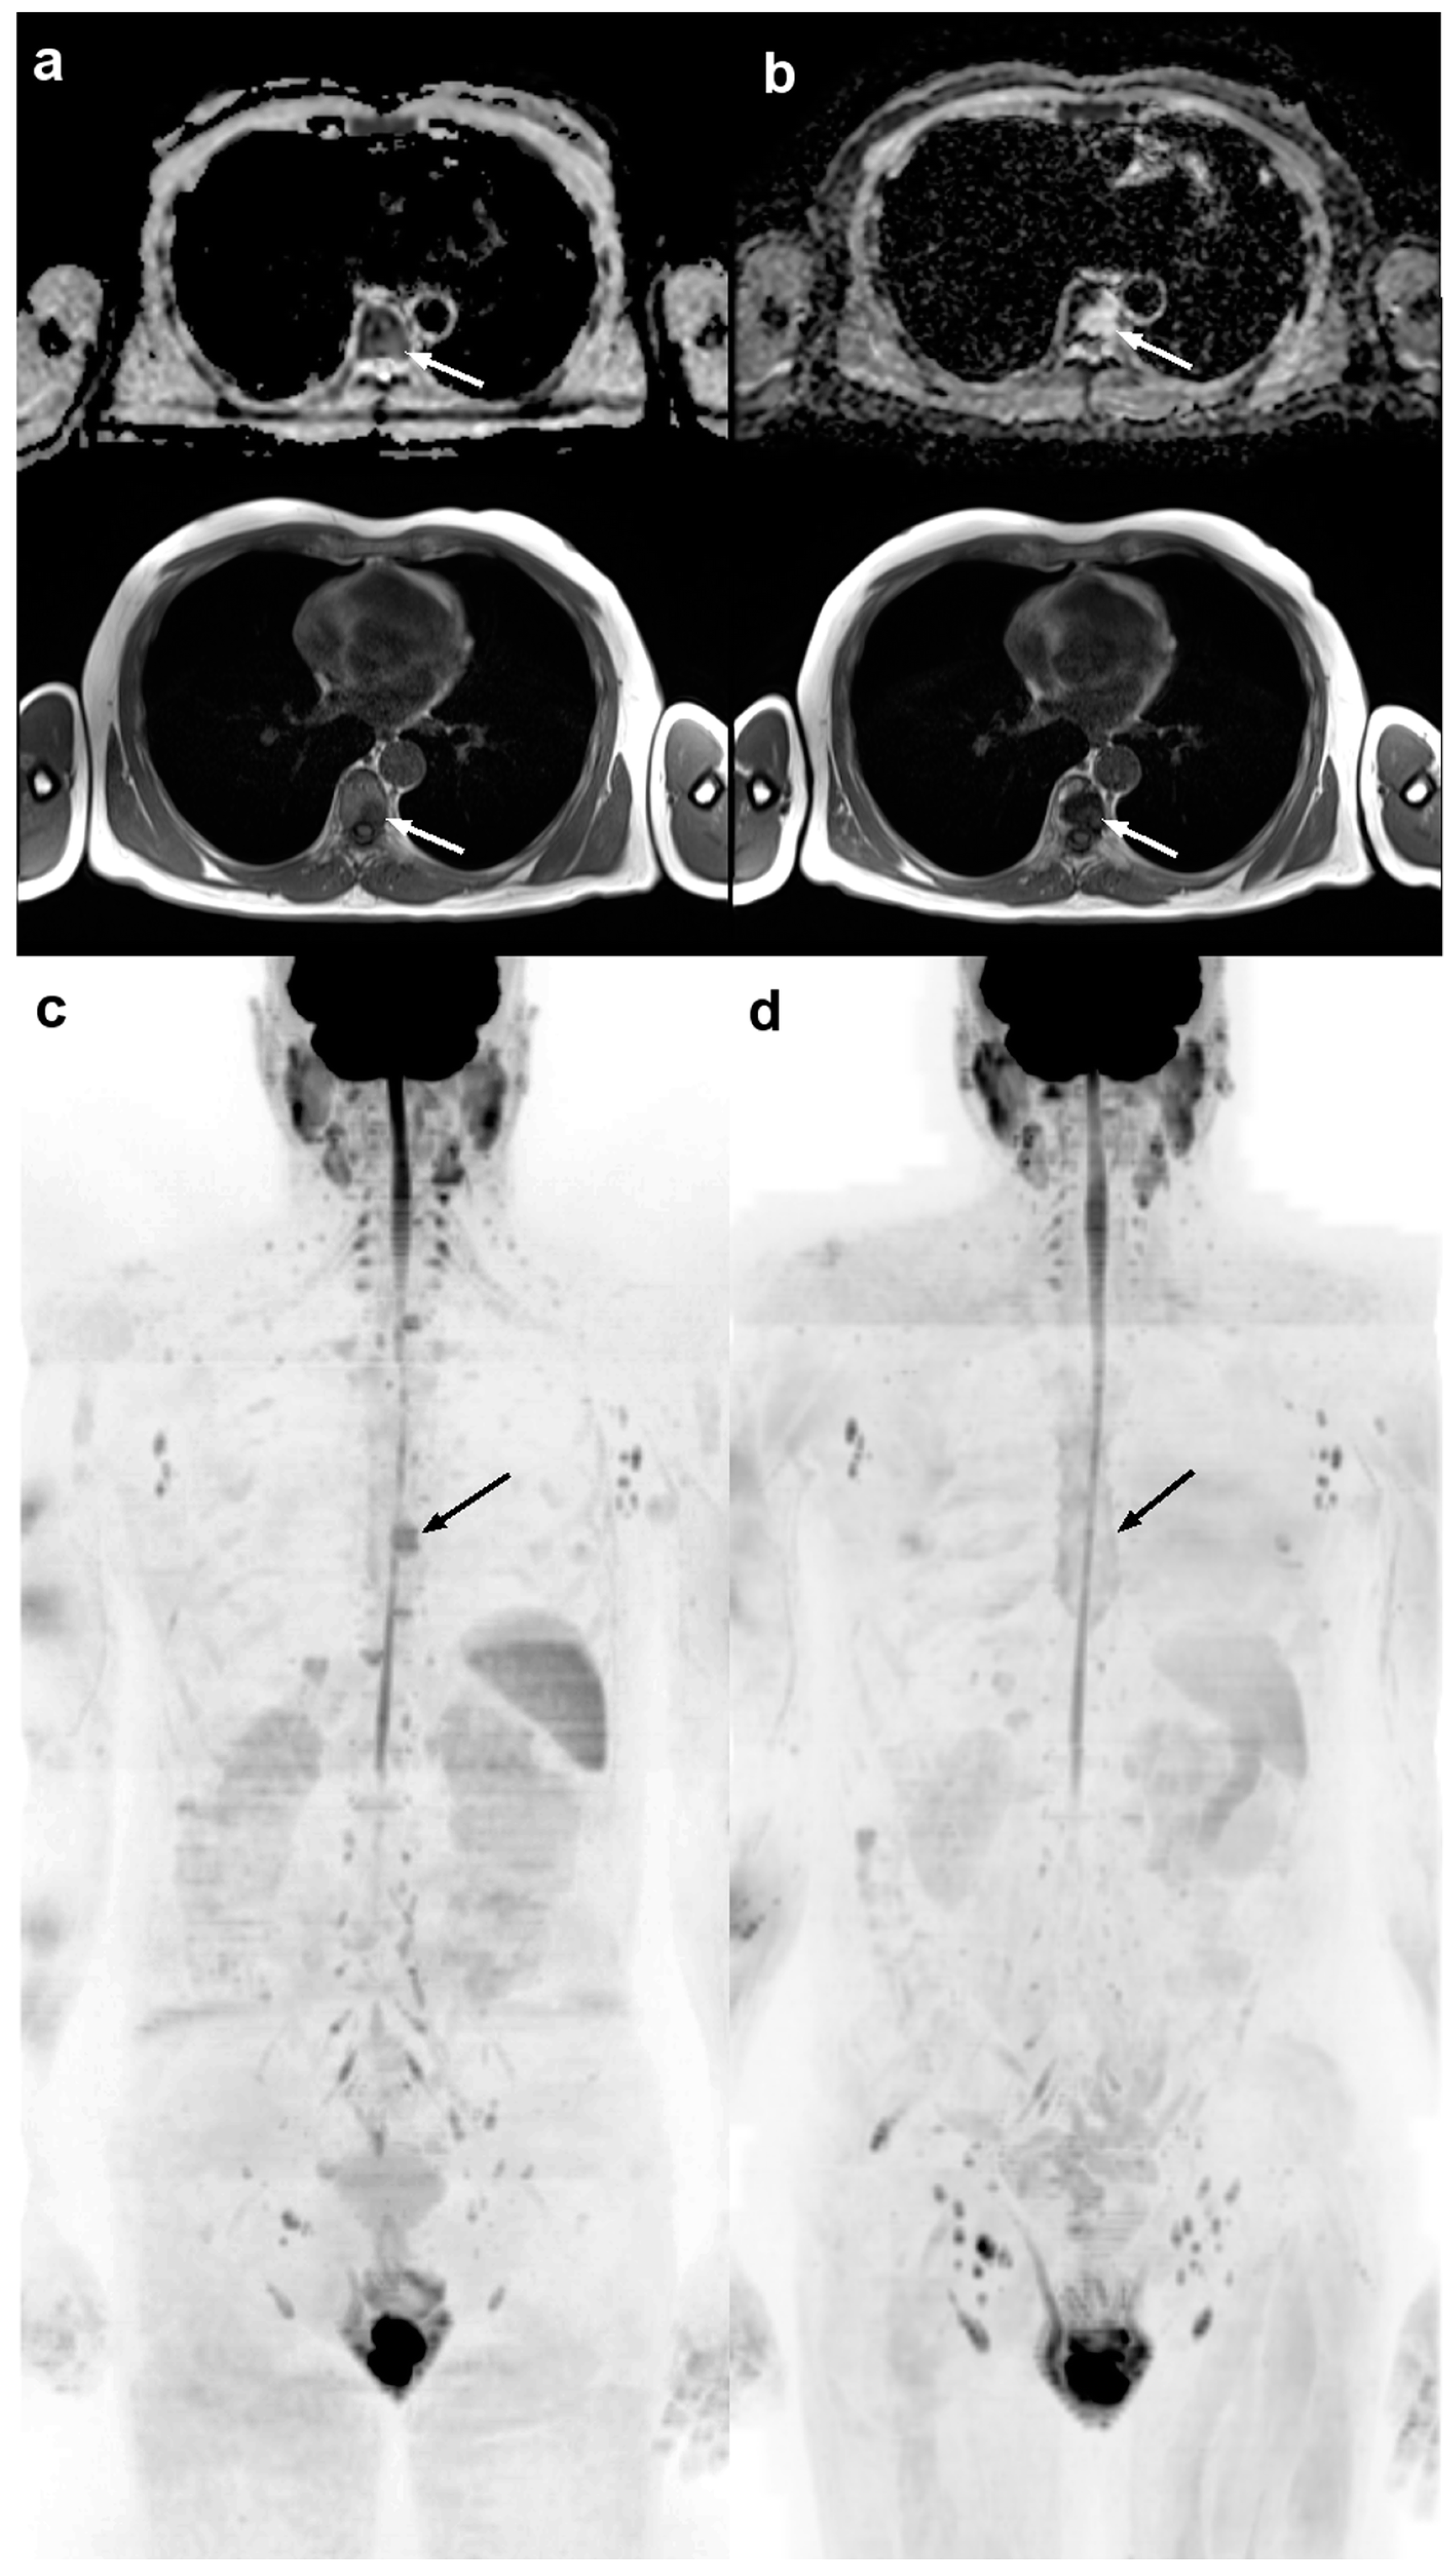

3. MET-RADS-P

3.1. Prognostic Role of MET-RADS-P

4. MY-RADS

4.1. Prognostic Role of MY-RADS